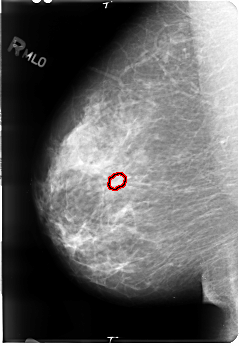

B_3039_1.RIGHT_MLO

FILE: B_3039_1.RIGHT_MLO.OVERLAY

TOTAL_ABNORMALITIES 1

ABNORMALITY 1

LESION_TYPE MASS SHAPE OVAL MARGINS CIRCUMSCRIBED

ASSESSMENT 3

SUBTLETY 3

PATHOLOGY UNPROVEN

TOTAL_OUTLINES 1

BOUNDARY